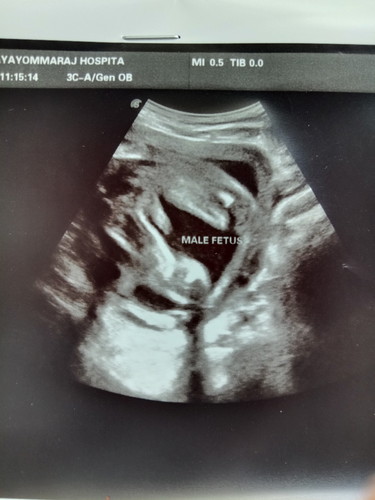

คุณแม่บ้านอื่น ได้ลูกสาวลูกชายกันค่ะ บ้านนี้ ซาวด์ 5เดือนกว่า ได้ผู้ชาย หมอบอกเห็นชัดมาก ?

มาเป็นแท่งเยยยย ☺️💕 บ้านนี้สาวน้อยค่ะ มาเป็นกลีบชัดเหมือนกัน 😂